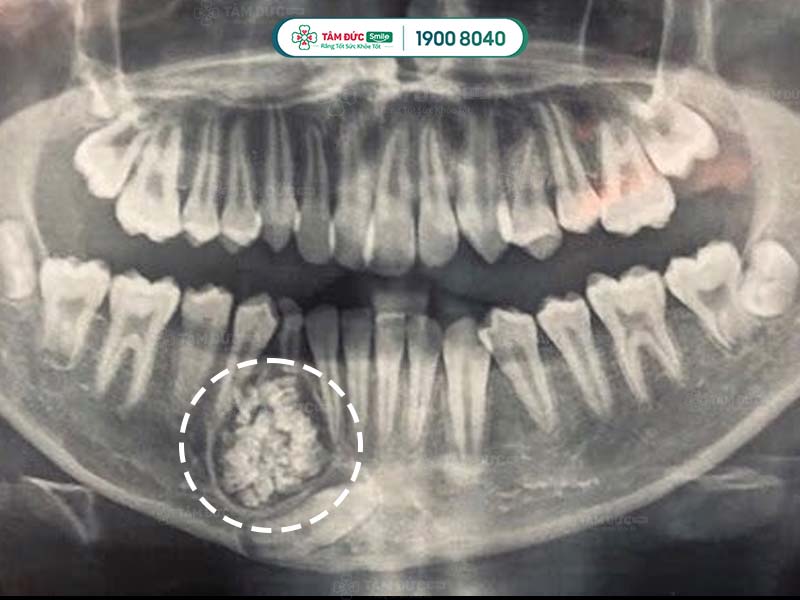

U răng qua phim chụp X-Quang

1.1. U răng đa hợp

- Thường xuất hiện ở vị trí hàm răng trên.

- Ở u răng đa hợp, răng vẫn còn 3 mô răng riêng biệt là: men răng, ngà răng và xương răng. Có thể vẫn có thùy răng.

1.2. U răng phức hợp

- Thường xuất hiện ở vị trí hàm răng dưới.

- U răng phức hợp giống như một khu vực cản quang với các mật độ u khác nhau ở từng dạng bệnh.